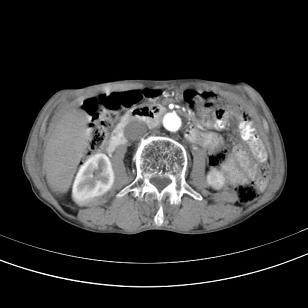

标题: 男,65岁,反复右上腹痛, [打印本页]

标题: 男,65岁,反复右上腹痛,

胃镜提示十二指肠占位